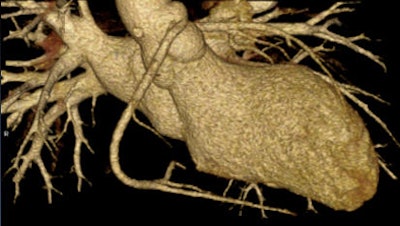

| High-pitch scan showing anomalous right coronary artery in a 17-year-old patient. Image courtesy of Dr. B. Kelly Han. |

Using an aggressive beta-blockade protocol to lower heart rates, combined with low-dose imaging and high-pitch scan techniques, the researchers were able to obtain excellent images of the coronary arteries in patients as young as 5 months, she said.